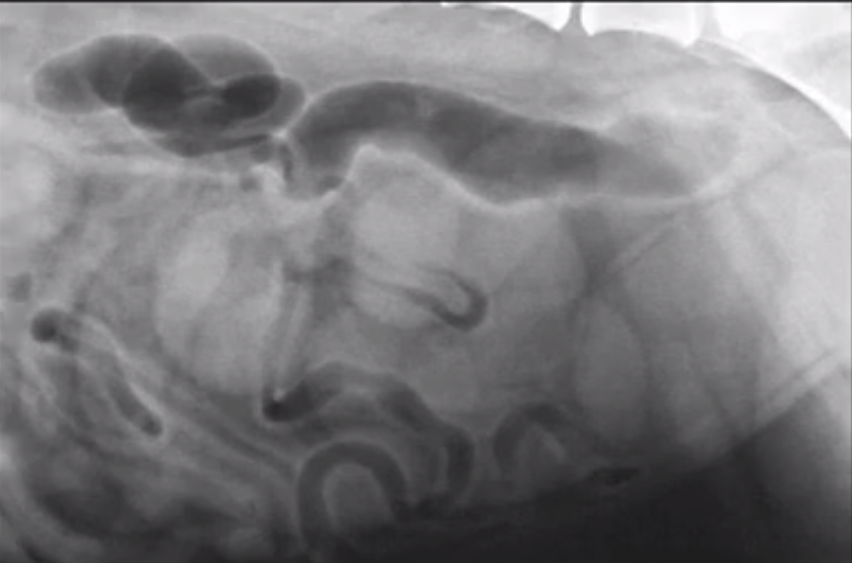

What does this image show?

General dilation